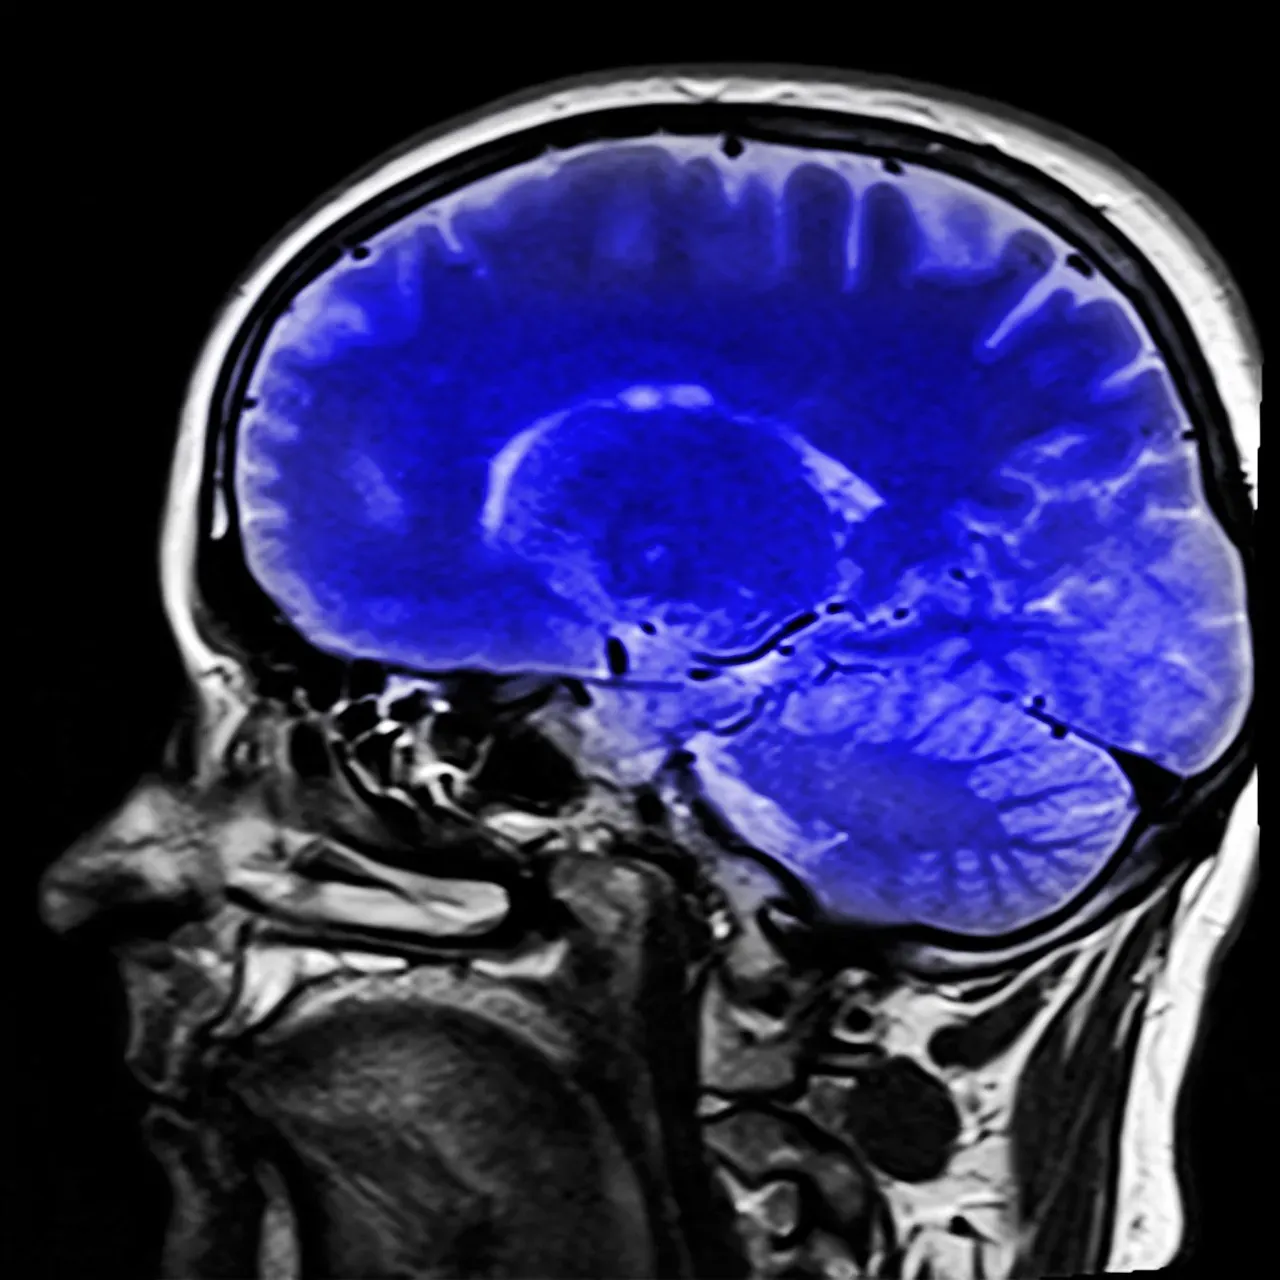

Scientists have used advanced brain imaging to watch what happens during placebo responses. The results are remarkable, showing concrete changes in brain chemistry and activity patterns.